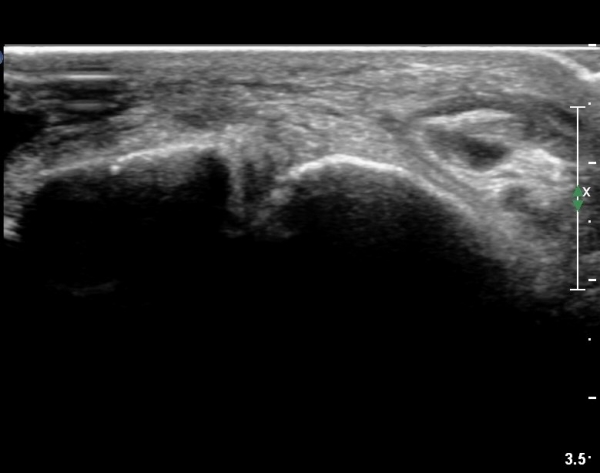

¹ß¸ñ ¾ÕÂÊ Á¾´Ü¸é°Ë»ç¿¡¼­ ¹ß¸ñ°üÀý³» °æ¹ÌÇÑ ¼ö¾×Àú·ù¸¦ º¸À̰í(»çÁø 1, 2)

°Å°ñÁÖ»ó°ñ°üÀýÀÇ ¼ö¾×Àú·ù°¡ °üÂûµÈ´Ù(»çÁø 3).